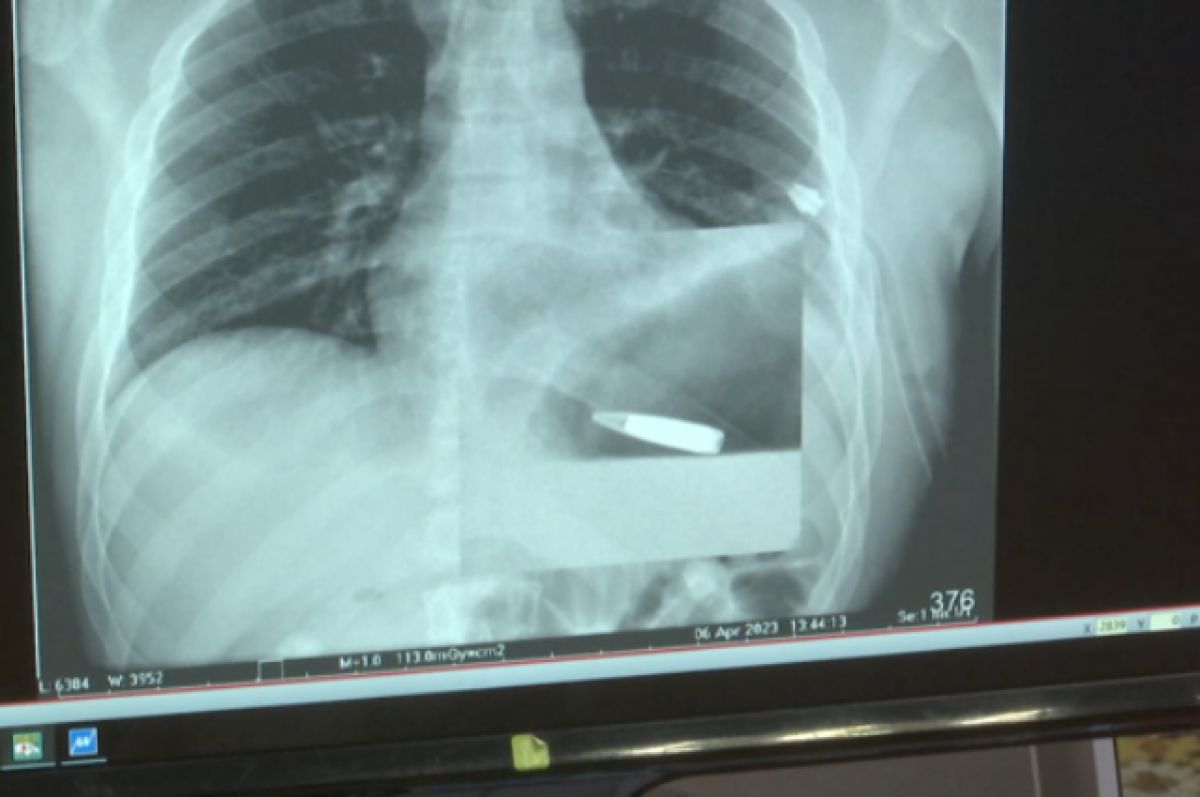

Yekaterinburqdakı 23 nömrəli xəstəxanaya ağır vəziyyətdə güllə yaraları almış xəstə gətirilib. Təcili yardım şöbəsində cərrah və anestezioloqlardan ibarət növbətçi qrup qurbanı müayinə etdi, yaraları müalicə etdi və iki gülləni çıxardı.

Medicina.az xəbər verir ki, kompüter tomoqrafiyası müayinəsi sinədə üçüncü güllənin olduğunu aşkar etdi.

İki saatlıq əməliyyat zamanı tibb qrupu gülləni çıxardı və ürək yarasını tikdi. Kütləvi qan itkisini əvəz etmək üçün kişiyə təxminən 1,5 litr donor qanı verildi. Onun döş sümüyünün xüsusi metal məftillə bağlanması və xəstə sonradan doqquz gün süni tənəffüs aparatında reanimasiyada keçirdi.